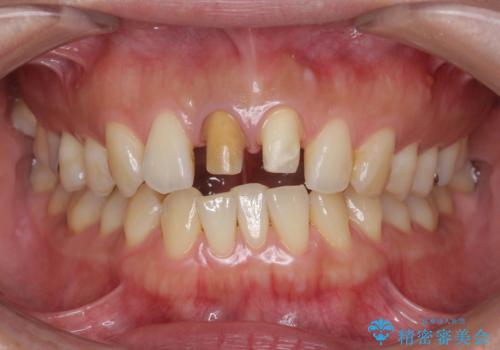

- 前歯の変色の改善を求めて来院されました。

X線検査を行ったところ、共に深い虫歯が原因となり神経が死んでしまっている状態であることがわかり、根管治療を行ったのちセラミック補綴を行っていくこととなりました。

- 32万円(仮歯・ファイバーコア・ジルコニアクラウン×2)費用は治療当時の料金となります